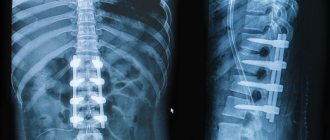

• Neurological problems. This could be nerve damage, hernia (in the lumbar or sacral region).